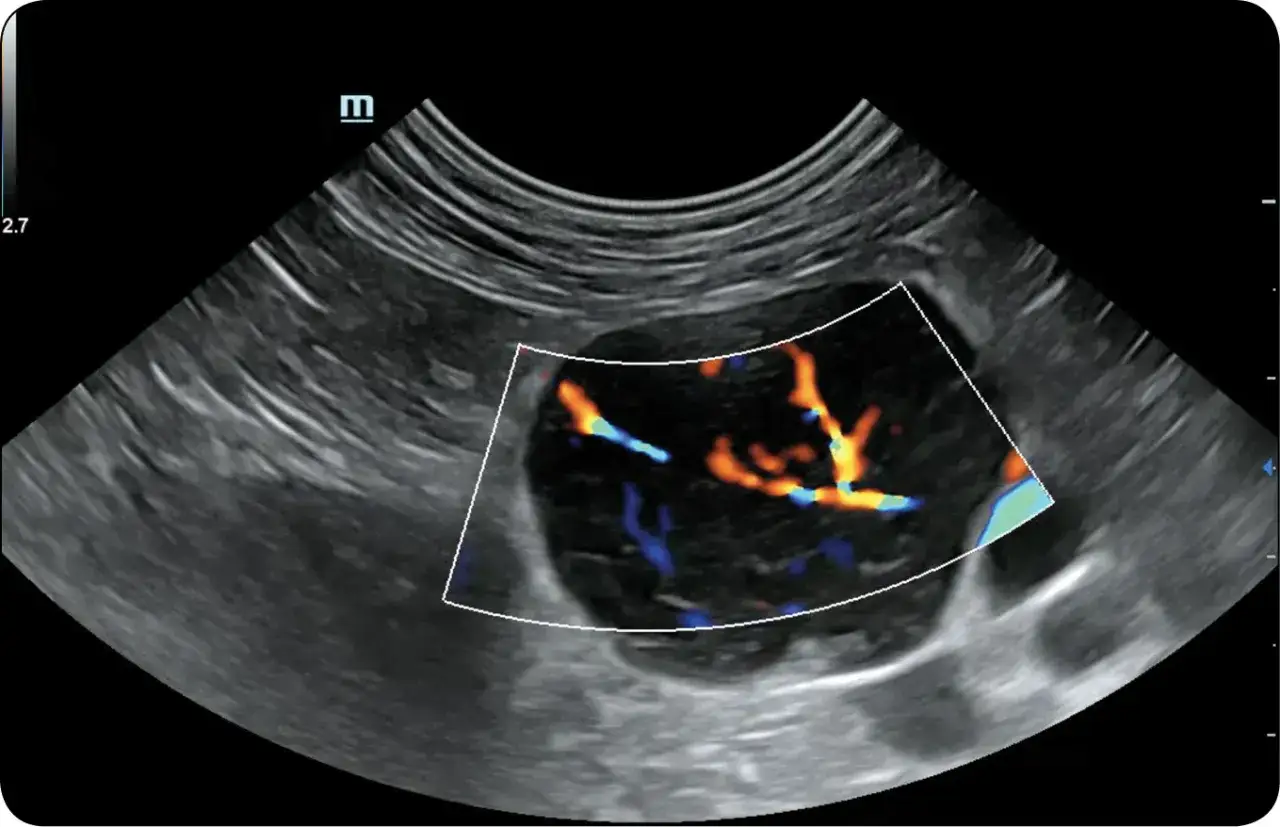

- USG jamy brzusznej pokazuje zgrubienie ściany jelit i pozwala ocenić inne narządy.

| USG | Żeby ocenić jelita, węzły chłonne i inne narządy jamy brzusznej. |